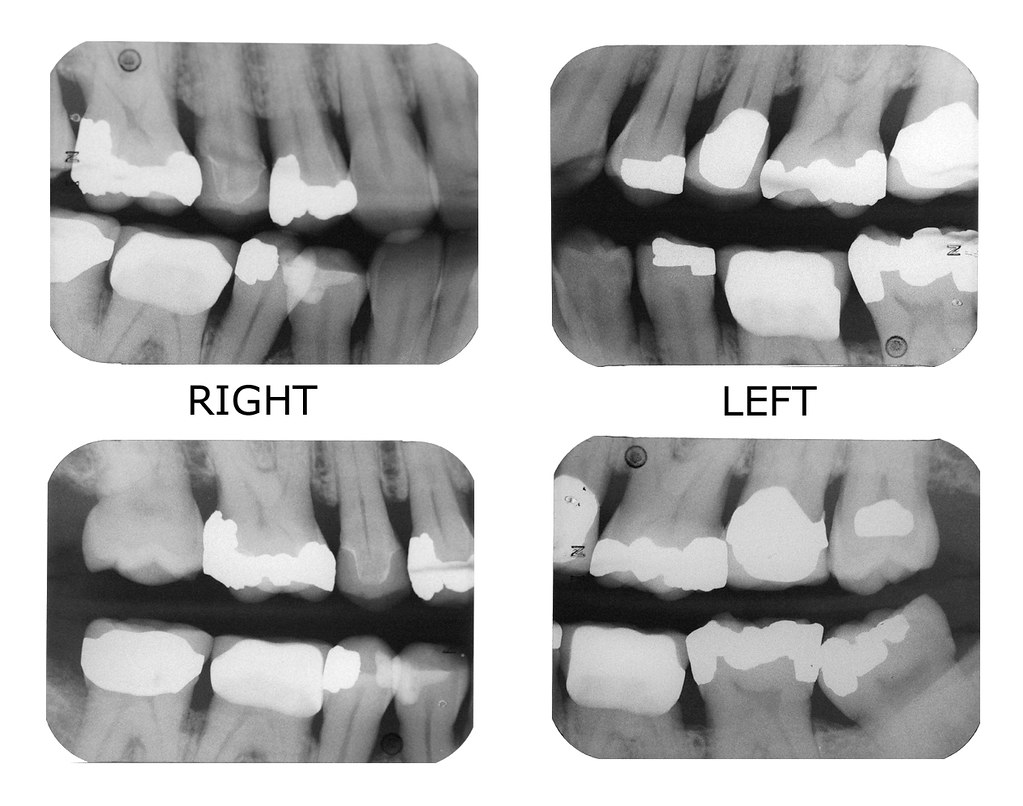

Bite Wings Typical set of four bite wing xrays. Sam Feinstein Flickr D0274 Dental X Ray 4 Bite This guide is published to educate dentists and others in the dental community on selection and reporting of diagnostic imaging procedures. This guide describes, for dentists and others in the dental community, the nomenclature and descriptor revisions for the four. The vertical bitewing positioning allows an image of up to two molars. D0274 Dental X Ray 4 Bite.